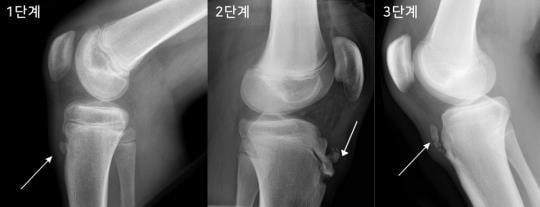

증상은 무릎 아래 정강이에 통증이 있는데 꿇는 자세나 태권도, 축구 등을 심하게 하거나 운동을 하지 않았지만, 일상 생활 중 무릎을 우연히 부딪힌 경우 심한 통증이 유발될수 있다. 무릎의 동그란 접시뼈에서 정강이로 인대가 붙어있고 이 인대의 기능은 무릎을 펼 때 힘을 전달하는 기능을 한다. 태어날 때는 큰 뼈와 분리되어있지만 성장하면서 뼈가 큰 뼈에 부착이 되어야 한다. 그러나 그렇지 못하고 계속 뼈가 조그맣게 분리되어 있어 통증을 유발하는 병이다.

오스굿씨병은 뼈 성장이 빠르게 일어나는 성장기 연령에서 흔하지만 특히 무릎을 많이 사용하는 운동선수, 군인과 같은 성인에게서도 발생한다.